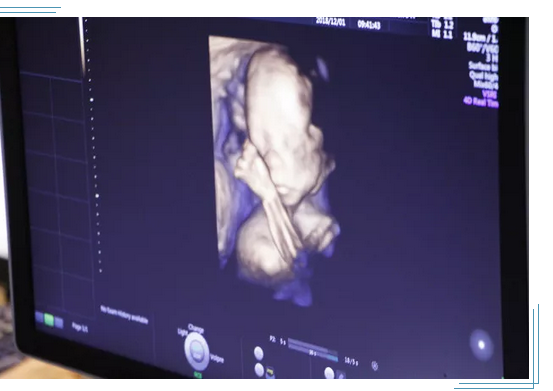

大连孕妈做四维彩超需要注意什么?因为四维彩超能够立体显示胎儿的颜色、面、各器官的发育情况,甚至能够将胎儿的一颦一笑描绘清晰的呈现在孕妈妈面前的彩色超声设备,自出现以后就备受孕妈妈的欢迎,所以怀孕的准妈妈们自然会关心检查的费用。那么,大连孕妈做四维彩超需要注意什么?

1、做四维彩超注意时间:一般来说女性怀孕期间12-30周都是可以进行四维彩超检查的,但是合适的检查时间是在22-28周,这个时期胎儿的结构已经形成,胎儿的大小和羊水量适中,能够清楚的看到胎儿的体表。

3、孕妇做四维彩超过程:四维彩超主要是检查胎儿的面部、大脑、骨骼、心脏、脊椎等有无发育缺陷,如果发现了异常可能进行的时间久比较长了,做四维彩超的整个过程大约在30分钟左右。

为了每个家庭都能拥有一个健康宝宝,大连美琳达妇儿医院斥巨资率先引进新一代·美国GE-E10四维彩超。GE-E10四维彩超能够表面成像,若胎儿有唇腭裂、四肢发育畸形、脑膜膨出、脊柱裂、腹壁裂等先天畸形,都能更清晰地查出来,也有利于医生做出判断。